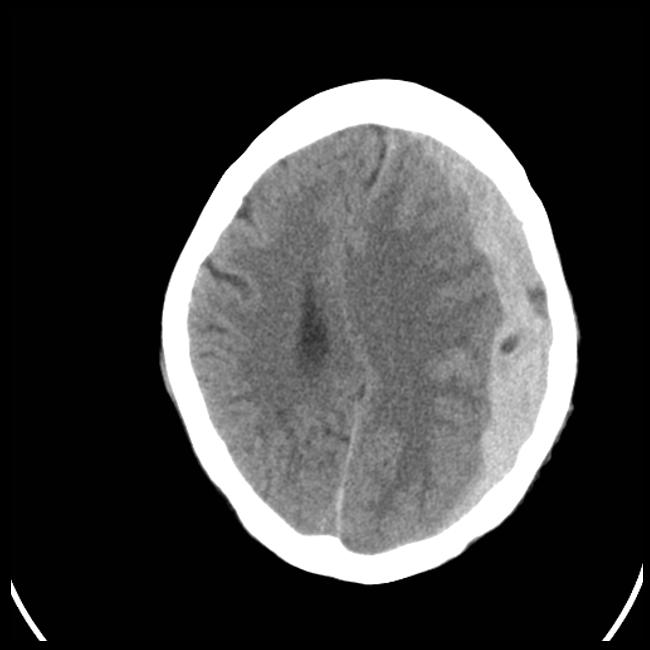

- Classification of hemorphage using Topological Data Analysis combined with CNN (project realised for course ‘Medical Imaging’)